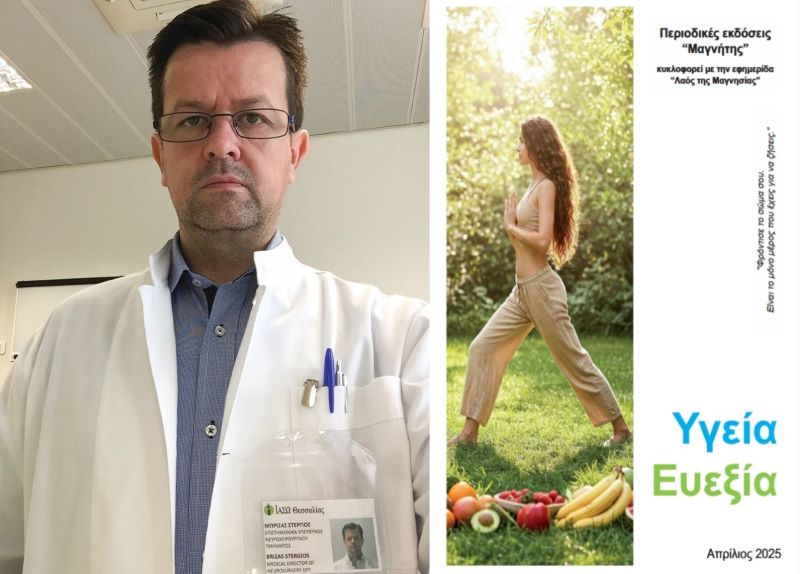

Δισκοκήλες αυχενικής μοίρας σπονδυλικής στήλης / Νευροχειρουργική αντιμετώπιση – Γράφει ο Στέργιος Μπρίζας

Γράφει ο Μπρίζας Στέργιος

MD, MSc, Νευροχειρουργός

Διευθυντής Β΄ Νευροχειρουργικής κλινικής

ΙΑΣΩ Θεσσαλίας